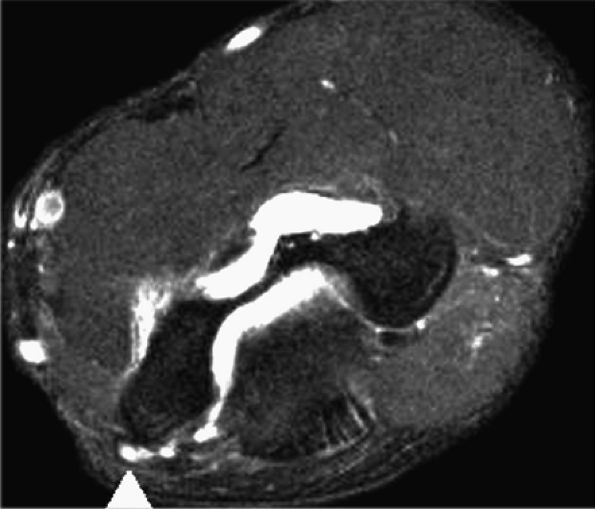

FIGURE 12.23 ● Ulnar neuritis. Axial fat-suppressed T2-weighted image shows thickening and increased signal within the ulnar nerve (arrowhead). Note associated edema and partial tear of the common flexor tendon (arrow).

|